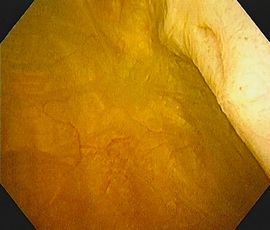

[尿管結石] 手術:経尿道的尿路結石破砕術(TUL)

手術画像